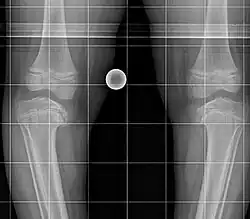

Die Blount-Krankheit, auch Blount-Syndrom oder Erlacher-Blount-Syndrom ist die kindliche Form der Tibia vara (beim Menschen), einer Deformation des Unterschenkelknochens infolge einer Wachstumsstörung der medialen Wachstumsfuge. Die Krankheit wurde nach dem Erstbeschreiber Walter Putnam Blount (1900–1992) benannt. Die Krankheit ist selten, jedoch unter der afrikanischstämmigen Bevölkerung Südafrikas häufiger anzutreffen.

Zwei Formen können unterschieden werden:

- Infantile Form bei Kindern unter 10 Jahren, meist bereits in den ersten Lebensjahren, in der Regel beidseitig auftretend

- Adoleszente, juvenile oder Spätform meist zwischen 8 und 15 Jahren und einseitig auftretend häufig mit vorzeitigem Verschluss an der Wachstumsfuge als auch Nekrosen an der benachbarten Epiphyse[1].